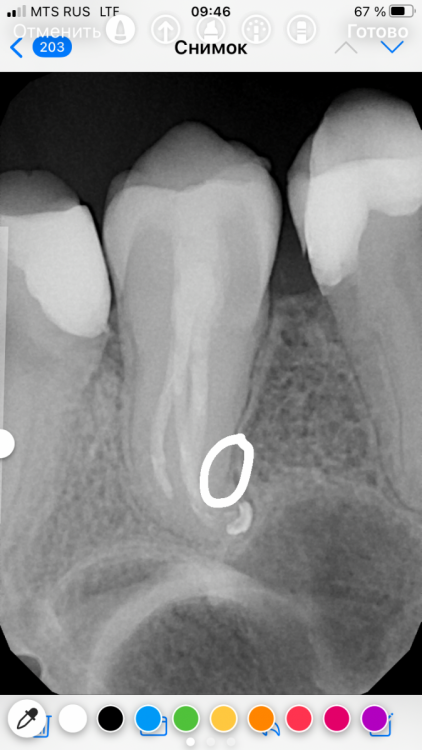

Mel17 Опубликовано 8 сентября, 2021 Поделиться Опубликовано 8 сентября, 2021 Здравствуйте! Подскажите пожалуйста, 26 зуб после эндодонтии, полтора года назад была эндодонтия, по снимку есть выход за апекс немного, но это никак не беспокоило все время, была 3 недели назад механическая трамва ( прикусила косточку на эту сторону челюсти), с тех пор как ощущаю как будто дискомфорт на этот зуб (по ощущениям как чувство распирания и отека, но визуально Отека нет). На десне появилось небольшое пятна к месту прилегание зуба к десне. Врач на Приём посмотрел, сказал на прошлом приеме до травмы 2 недели назад десна была намного Лучше... по кт и прицельному снимку признаков нет. Какие исходя из вашей практики признаки vfr и через какое время должно быть проявление на десне (одиночный карман) и рентгенологические признаки ? Спасибо... Ссылка на комментарий

Mel17 Опубликовано 14 сентября, 2021 Автор Поделиться Опубликовано 14 сентября, 2021 @dentikl подскажите пожалуйста если ли на снимке признаки трещины? Ссылка на комментарий

red_butler Опубликовано 14 сентября, 2021 Поделиться Опубликовано 14 сентября, 2021 3 минуты назад, Mel17 сказал: подскажите пожалуйста если ли на снимке признаки трещины? нет Ссылка на комментарий

Mel17 Опубликовано 14 сентября, 2021 Автор Поделиться Опубликовано 14 сентября, 2021 @red_butler Спасибо, а вот это тень так падает да, как затемнение чёрточкой ? Ссылка на комментарий

chervoncevdaniil Опубликовано 14 сентября, 2021 Поделиться Опубликовано 14 сентября, 2021 Рентгенологически трещину увидеть очень сложно,на ранних этапах чаще всего невозможно. Чаще всего когда рентген картина будет,то там и без снимка по жалобам и объективному осмотру будет ясно что она есть Ссылка на комментарий

St. Опубликовано 15 сентября, 2021 Поделиться Опубликовано 15 сентября, 2021 14.09.2021 в 10:59, Mel17 сказал: это тень так падает да, как затемнение чёрточкой ? Это так поверхности корней друг на друга накладываются. Ссылка на комментарий